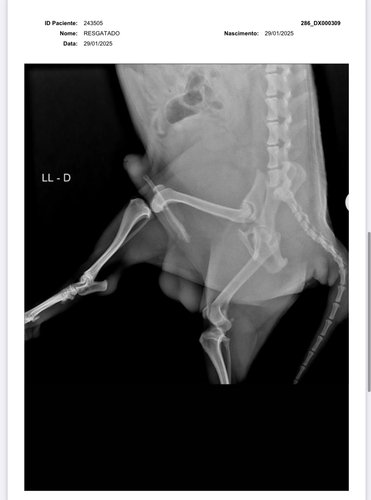

olá, eu sou a Samira, ajudo em uma ong de animais em Vilhena-RO e também resgato animais por conta própria. Encontrei esse pequeno cachorrinho abandonado a dias na chuva, sentindo tanta dor a ponto de não aceitar um sachê de comida. Levei ao veterinário e após buscar vários orçamentos, cheguei ao valor da vakinha, juntamente com a clínica Veterinária SOS animal, para a cirurgia do pequeno guerreiro. Não possuo condições de arcar com 100% da cirurgia, portanto, peço encarecidamente a ajuda de vocês para me ajudar e salvar a vida desse pequeno guerreiro. * Deixo abaixo o orçamento e os exames !